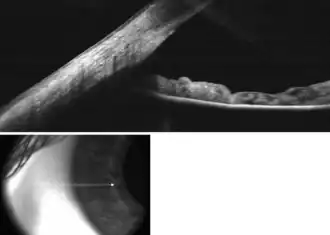

![]() Enlarged general view of the iridial angle. (When enlarged, visible with older label of 'trabecular tissue') | |

The trabecular meshwork is an area of tissue in the eye located around the base of the cornea, near the ciliary body, and is responsible for draining the aqueous humor from the eye via the anterior chamber (the chamber on the front of the eye covered by the cornea).

The tissue is spongy and lined by trabeculocytes; it allows fluid to drain into a set of tubes called Schlemm's canal which is lined by endothelium with blood and lymphatic properties that allow aqueous humor to flow into the blood system.[1]